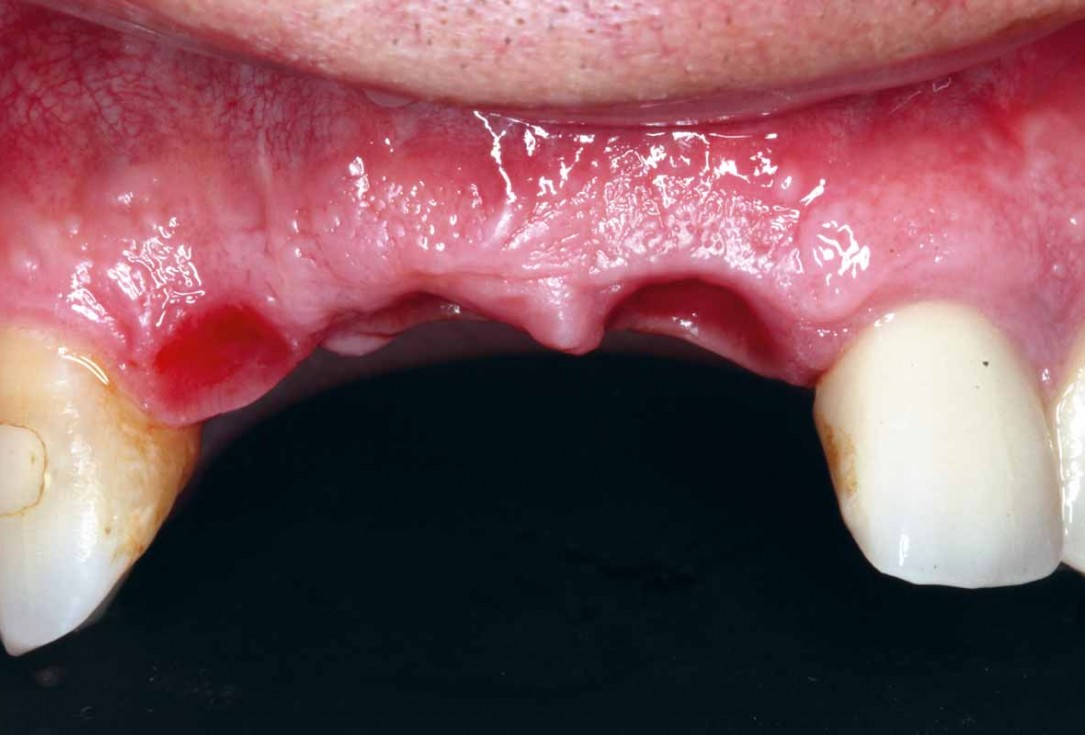

2/27 - Bone defect after raising the flap

GBR and soft tissue augmentation with cerabone® and mucoderm® - H. Maghaireh & V. Ivancheva